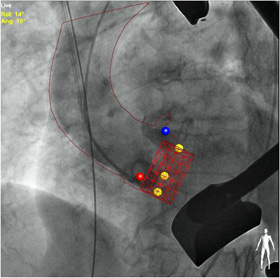

ライブ画像に指先で直接書き込める描画ツール「Marker tool」

「Marker tool」は,手元の操作パネル(TSM:タッチスクリーンモジュール)上で指先やマウスを使ってライブ画像上に血管・ステント等の形状を描画することができます。画像をズーム,パンニングにも追従し,スムーズな操作性を実現します。